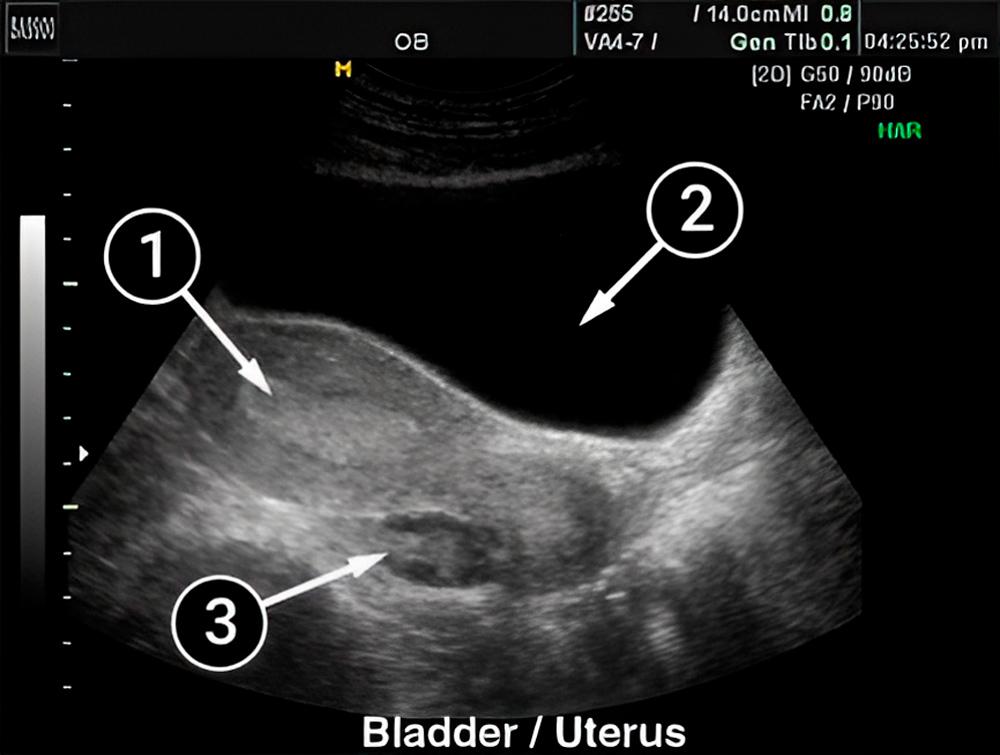

Lo que podemos ver en un ultrasonido

Dentro del útero, la mucosa se hace espesa, aumenta el suministro de sangre y todo se prepara para la posible implantación de un óvulo fertilizado. En la primera imagen se ve el contorno en forma de pera del útero sobre el fondo de una sombra oscura, que es la vejiga.

Dentro del útero, el área brillante es el endometrio, que recubre las paredes del útero. Durante este tiempo, el endometrio se espesa entre 7 y 10 mm más.

Debajo del útero se puede ver un ovario en forma de nuez. A juzgar por su forma y tamaño, la ovulación y maduración del cuerpo lúteo se producirá en el otro ovario.